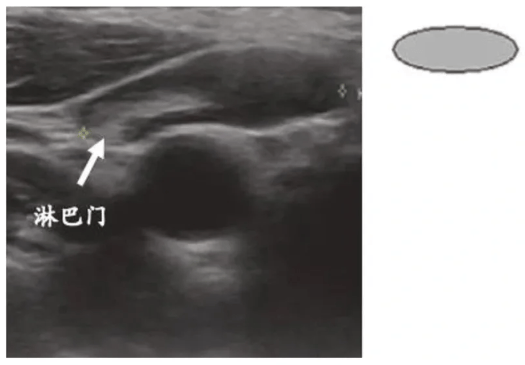

②反应性增生淋巴结(炎症/ 感染所致)

因局部炎症或感染,淋巴结可呈梭形或椭圆形肿大,长径可达1.5-2cm,但仍保持良性形态:淋巴门结构完整,回声均匀;血流从中央淋巴门向周边分支;无钙化、囊性变等可疑征象,属于良性肿大的淋巴结。